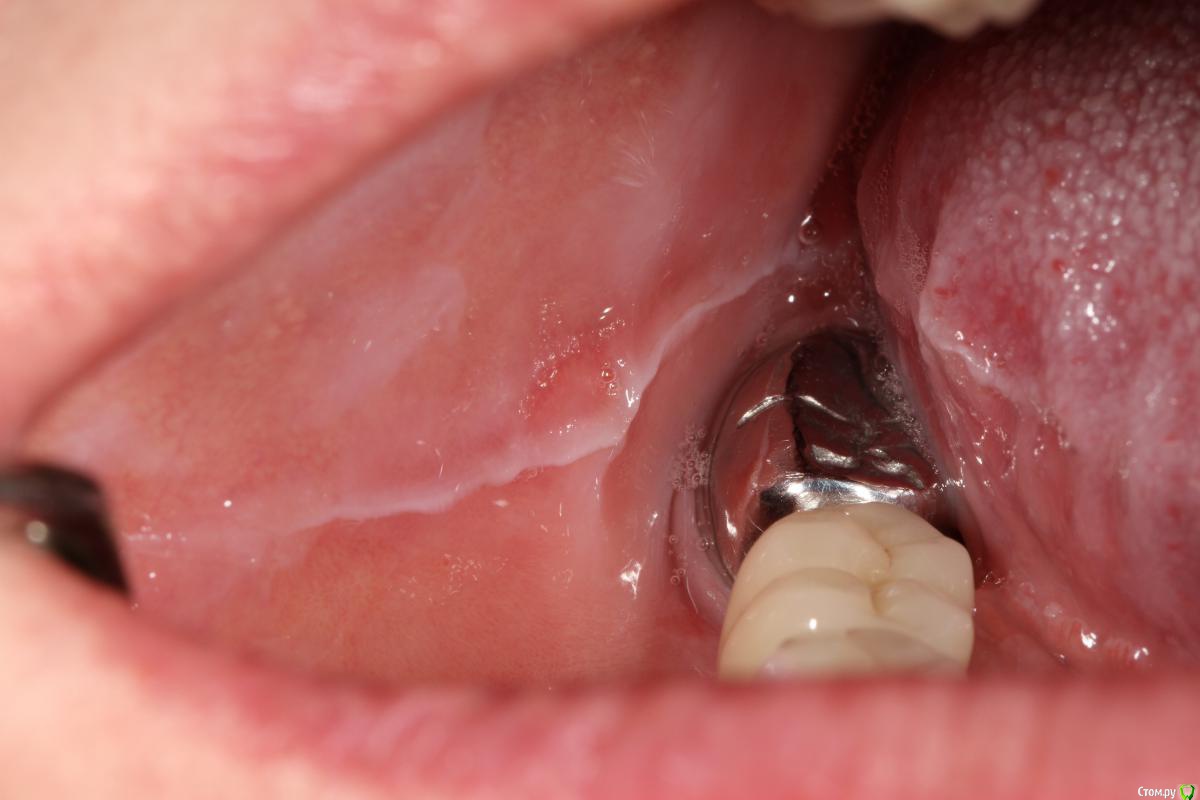

evodigit Опубликовано 21 мая, 2015 Поделиться Опубликовано 21 мая, 2015 Добрый день уважаемые коллеги, помогите советом.Пациентка два года назад была запротезирована у нас в клинике. Комбинированная работа, МК+ЦЛ. Через неделю пациентка обратилась с жалобами на разжевывание языка и щеки справа+ ощущение жжения языка. Коронки срезали, изготовили временные коронки в разных вариациях.( в общей сложности пациентка ходила с временными 3 месяца) Были изготовлены новые постоянные конструкции. Через полгода пациентка обратилась в клинику с жалобами на разжевывание языка. Была изготовлена миорелаксирующая каппа, после чего пациентка отмечает улучшение ситуации. Недавно пациентка обратилась в клинику опять с жалобами на разжевывание языка. Ситуация ухудшилась после того как пациентка реже стала носить каппу. До нашего лечения у пациентки стоял штампованный мост 10 лет. С чем может быть связана проблема? как ее решить? Заранее спасибо Ссылка на комментарий

chernov Опубликовано 23 мая, 2015 Поделиться Опубликовано 23 мая, 2015 evodigit вы сами себе противоречите про каппы.то есть положительная динамика(в первом сообщении),то нет.на какой цемент вы каппы ставите вообще не понятно...вообще эти отметины признак брукс компонента,скорее всего на н\ч в оласти 3-тих 4-рех зубов есть утолщение костной ткани.если да,то точно пациент бруксирует.а вследствии чего-это другой вопрос.возможно ваше протезирование и послужило толчком к этому(у пациента(ки) возможно горизонтальный тип жевания и так как ранее стояли плоские коронки было комфортно,а более выраженные новые конструкции организм пытается стереть,ИМХО,конечно).поэтому ищите причину,тем более пациентка отмечала улучшение после изготовления миорелаксирующей каппы,а если учесть,что каппа и срелаксировала мышцы и разомкнула зубы(дав горизонтальную свободу),то... Ссылка на комментарий